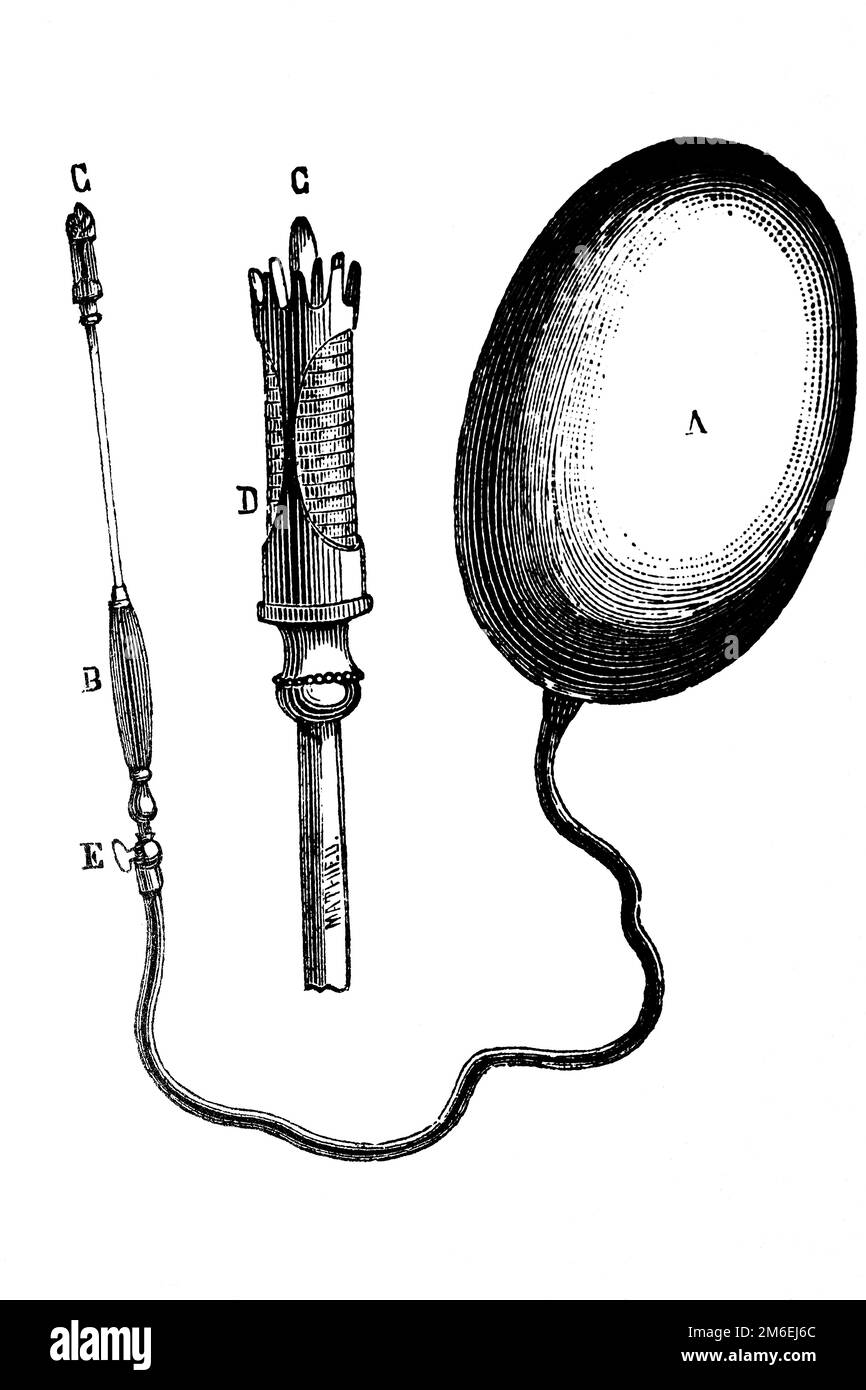

Sonde. Instrument utilisé pour pratiquer le cathétérisme. Illustration ancienne d'un livre médical. 1889. Banque D'Imageshttps://www.alamyimages.fr/image-license-details/?v=1https://www.alamyimages.fr/sonde-instrument-utilise-pour-pratiquer-le-catheterisme-illustration-ancienne-d-un-livre-medical-1889-image503110357.html

Sonde. Instrument utilisé pour pratiquer le cathétérisme. Illustration ancienne d'un livre médical. 1889. Banque D'Imageshttps://www.alamyimages.fr/image-license-details/?v=1https://www.alamyimages.fr/sonde-instrument-utilise-pour-pratiquer-le-catheterisme-illustration-ancienne-d-un-livre-medical-1889-image503110357.htmlRF2M6EJB1–Sonde. Instrument utilisé pour pratiquer le cathétérisme. Illustration ancienne d'un livre médical. 1889.

Attention. Illustration ancienne d'un livre médical, 1889. Banque D'Imageshttps://www.alamyimages.fr/image-license-details/?v=1https://www.alamyimages.fr/attention-illustration-ancienne-d-un-livre-medical-1889-image503110228.html

Attention. Illustration ancienne d'un livre médical, 1889. Banque D'Imageshttps://www.alamyimages.fr/image-license-details/?v=1https://www.alamyimages.fr/attention-illustration-ancienne-d-un-livre-medical-1889-image503110228.htmlRF2M6EJ6C–Attention. Illustration ancienne d'un livre médical, 1889.